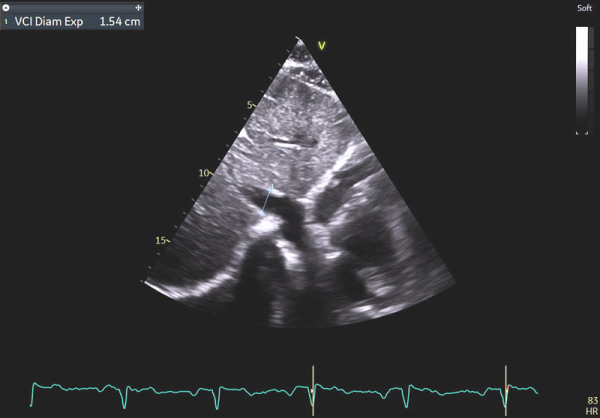

Image 10 : échocardiographie 2D en incidence sous-costale, mesure du diamètre de la veine cave inférieure

En effet, c’était le diagnostic à éliminer en priorité devant les symptômes présentés par la patiente avec un ECG légèrement microvolté et des éléments évocateurs d’une amylose cardiaque à l’échocardiographie : hypertrophie VG très minime mais > 10 mm chez une femme (> 11 mm chez un homme) (cf Vidéo 1 et Image 1), hypertrophie VD à 6 mm (>5 mm) (cf Image 9) et l’altération des strains longitudinaux basaux à l’AFI après valeurs préservées à l’apex (cf Image 7).

En cas d’atteinte précoce d’amylose cardiaque, ce sont en effet les premières anomalies à pouvoir être objectivées et il peut ne pas y avoir encore d’altération marquée du SLG (cf Image 7), de signe de dysfonction diastolique VG (cf Images 3 et 4), de dilatation de l’OG (cf Image 8), de dysfonction systolique du VD (cf Image 5) et les pressions peuvent être normales.